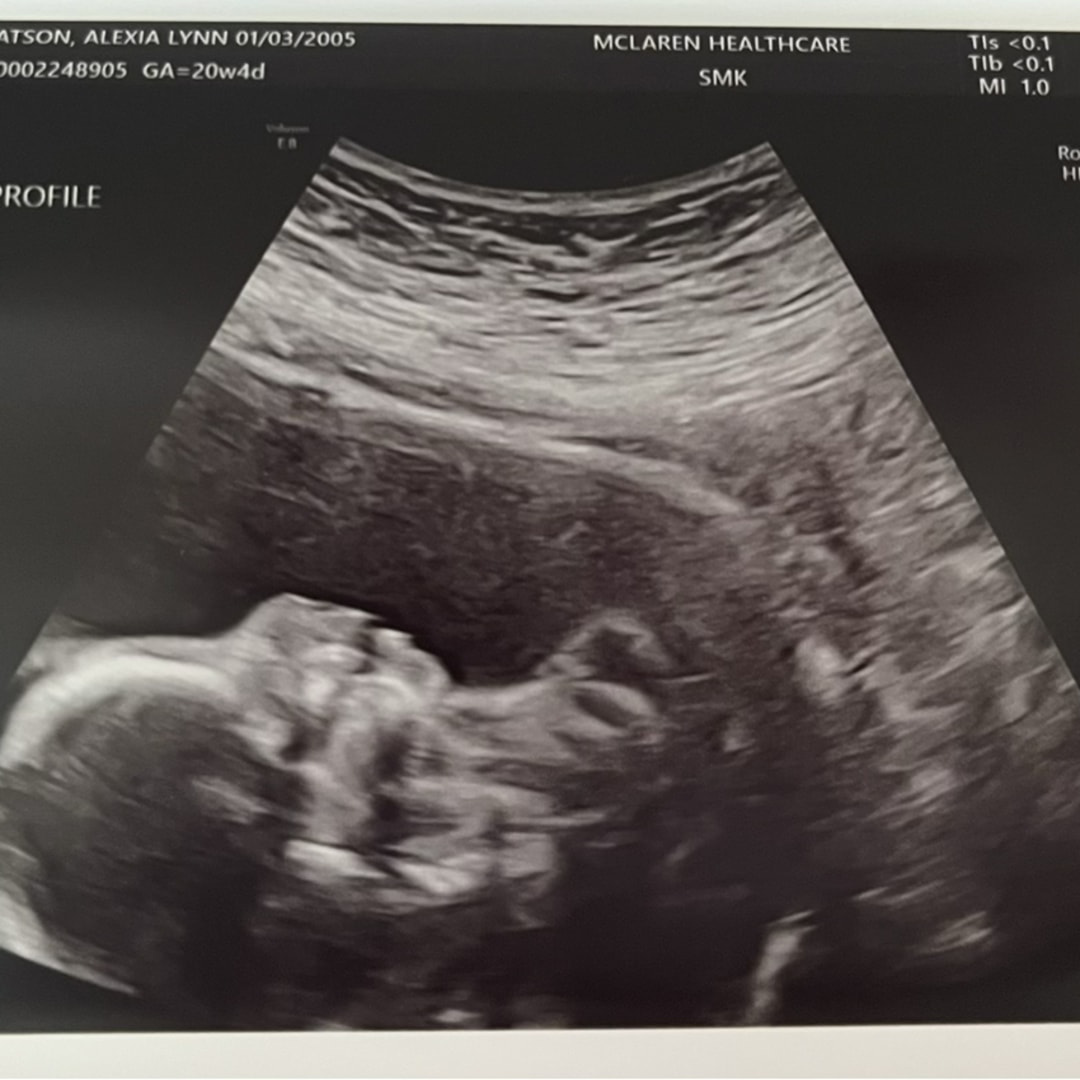

Hello everyone! Thank you for viewing our registry! ☺️ We are ready to welcome Madeline Jones Brewer in March 2026! 🩷

Pearhead "Love at First Sight" Sonogram Frame

babylist Icon

$12.99

target Icon

amazon Icon

from $9.99

I purchased this